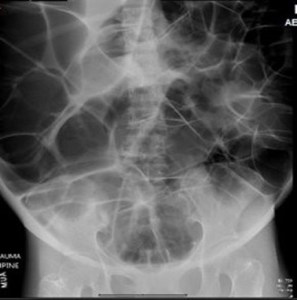

ED abdominal images and workup:

Significant lab results included a non-anion gap metabolic acidosis.

Figure 1. Anteroposterior (AP) abdominal plain film obtained in the ED.